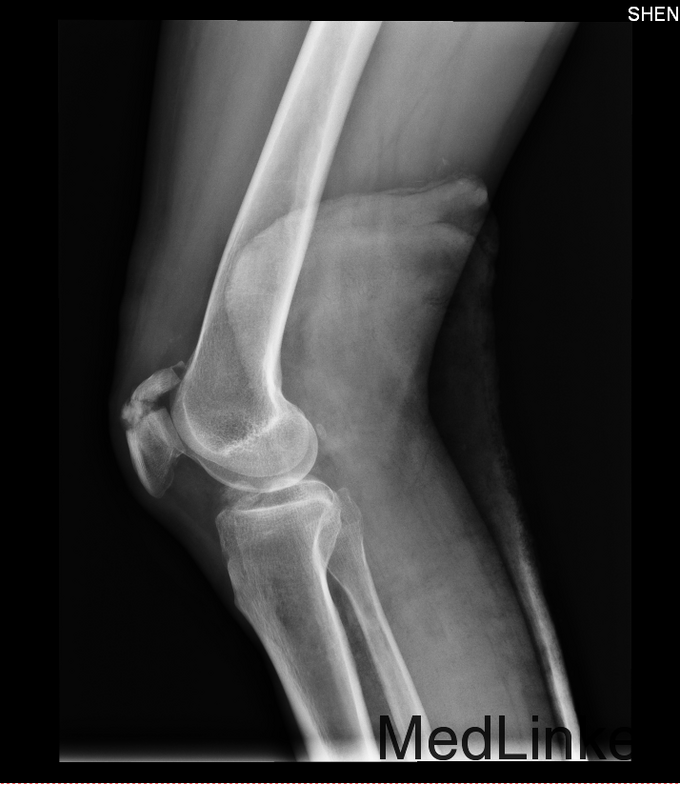

主诉:右侧膝关节疼痛活动受限4小时。现病史:4小时前骑摩托时发生车祸,患者当时头面部及右下肢受创,患者神志尚清楚,患者家属急送患者到当地县医院,行头部CT及右下肢DR检查,头部CT提示:右颞部硬膜下血肿可能性大,右下肢DR提示右侧髌骨粉碎性骨折,给予对症处理后患者症状未见好转.为求进一步治疗,患者家属急送患者到我院急诊,行头部CT检查提示右颞部硬膜下血肿可能性大.为进一步治疗,将患者转入我科.

专科查体:患者神志清楚,定位准确,额纹对称,闭目有力,双侧瞳孔等大正圆,D=3.5mm,对光反射灵敏,双侧眼球各方向运动充分,无复视及眼震。双侧鼻唇沟对称,示齿口角不偏,伸舌居中。右下肢髌骨骨折,左下肢肌力4级,肌张力正常,双上肢肢肌力5级,肌张力正常,深浅感觉粗查未见异常。右侧巴氏征未引,左侧巴氏征(-)。

诊断:右侧髌骨骨折,治疗:于麻醉下行髌骨骨折切开复位内固定术